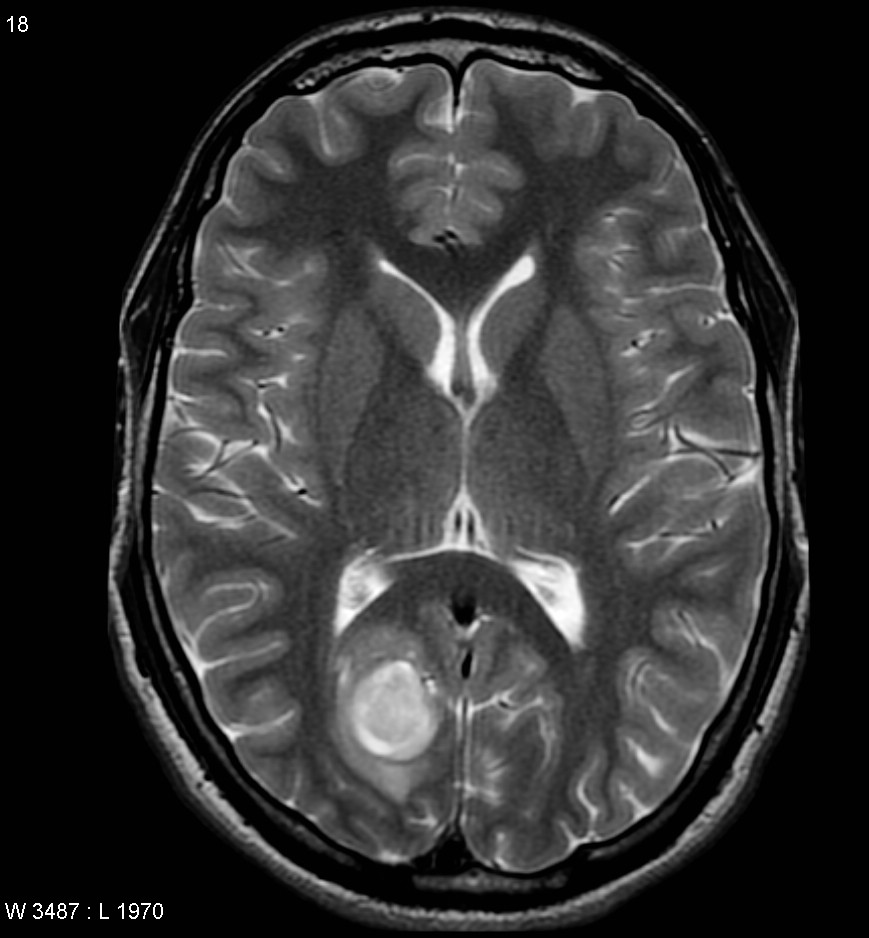

МРТ головного мозга: показания и результаты

Раздел: Визуальный дайджест